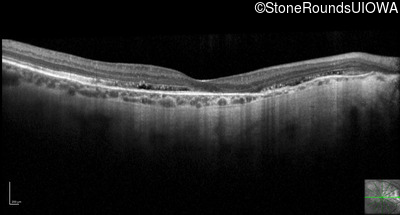

Optical Coherence Tomography - Left - 20/30 -2 sc

Exemplar / OCT Stack